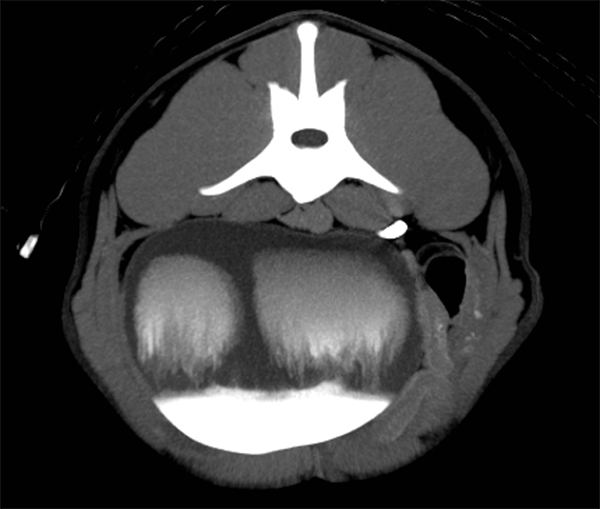

Médusée

Cette vessie de chien était médusée à l’arrivée du jet urétéral rempli d’iode. Mais rassurez-vous, l’urine ne s’est pas transformée en pierre, bien heureusement. 😉

Merci à notre amie Pascaline Pey de la Faculté de médecine vétérinaire de l’Université de Montréal pour cette découverte mythologique !